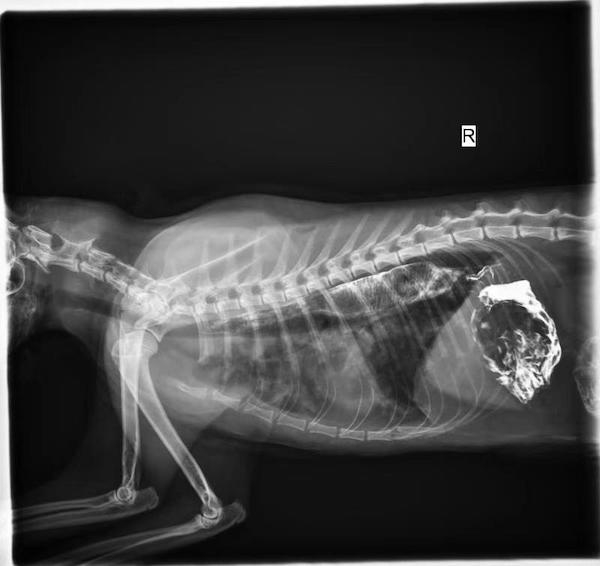

图说:戴小姐的宠物猫离世前拍的肺部感染的x光照片 来源/采访对象提供(下同)

谈及自己布偶猫Birkin离世,戴小姐仍哽咽不止。10月7日,Birkin突然开始腹泻,不愿进食,当晚就被送入闵行区金平路802号安安宠物医院。“做完X光和一系列检查后,医生说排除吞食异物可能,判断为肠胃炎。”于是,Birkin连夜开始输液治疗。10月8日,情况并未好转,依旧不吃不喝。10月9日,眼见爱猫情况更为糟糕,呕吐不断,戴小姐开始怀疑之前诊断结论。后来,医生对Birkin做完B超后发现,其胃内有大量积液,但并未发现异物。随后,医生让小猫灌食钡餐,做造影检查。“5小时内做了6次检查,这样连番被折腾,我真是心疼。”戴小姐说。